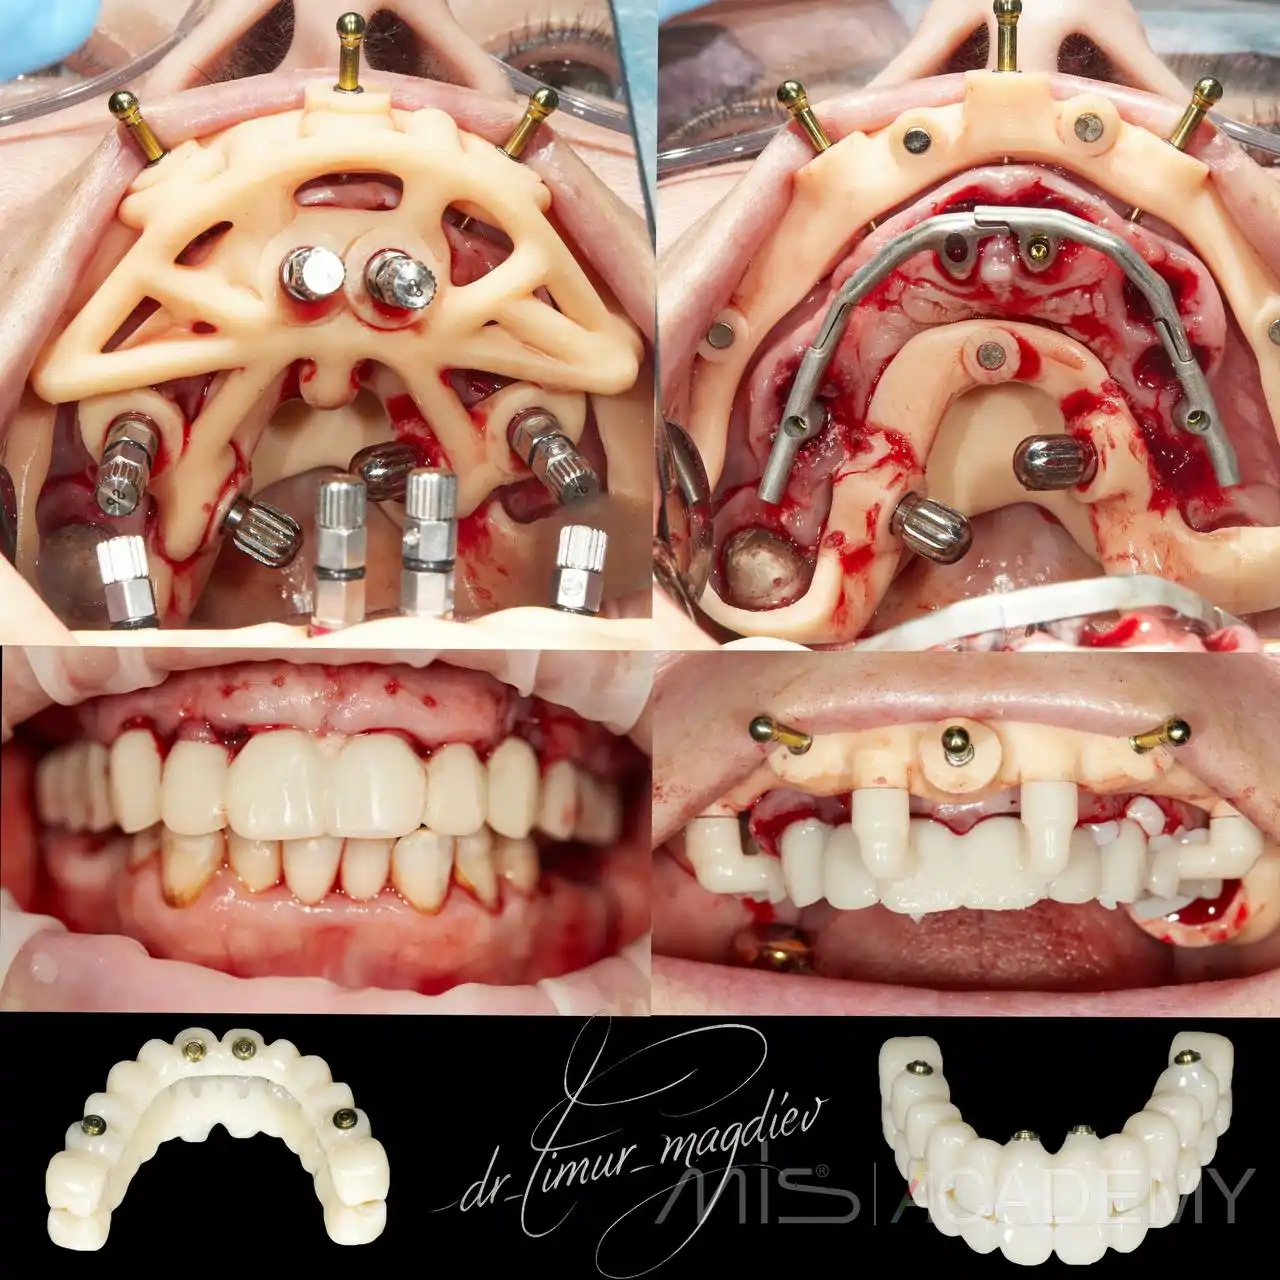

Комплексная реабилитация MIS Multi-fix.

— Циркониевая конструкция на 4х имплантатах.

Ортопед: Белобородцев Сергей Александрович.

Хирург: Тимур Магдиев